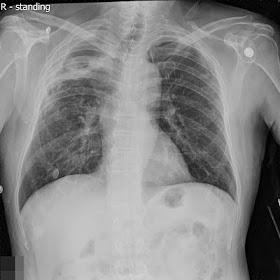

如上圖,88M, COPD with right pneumothorax history. Chest tightness for hours, HR120 beats/min, RR 32/min, BP 137/65 mmHg. PE: RLL decreased breath sound. EKG: RBBB pattern, no significant STT changes. Give O2 non-rebreathing mask 100% and oximeter showed SpO2 89%.

CK-MB, troponin-I normal limit.

Favor chest tightness due to interdependence in the lung (personal opinion)